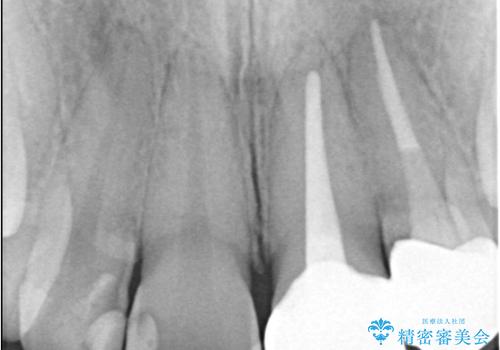

左上1番および2番は失活歯であり、両歯ともに失活に伴う変色を認めました。左上2番に関しては根尖部に透過像を認め、根尖性歯周炎と診断しました。これが前歯部の痛みの原因と考えられました。

左上2番に対して精密根管治療を実施し、感染源の除去を行いました。その後、左上1、2番ともにオールセラミッククラウンによる補綴を行い、審美的な修復を行いました。

根管治療では、ラバーダム、マイクロスコープ、根管をしっかり洗浄するための専用器具の使用が必須となる治療です。

徹底した洗浄により高い治療効果が得られます。